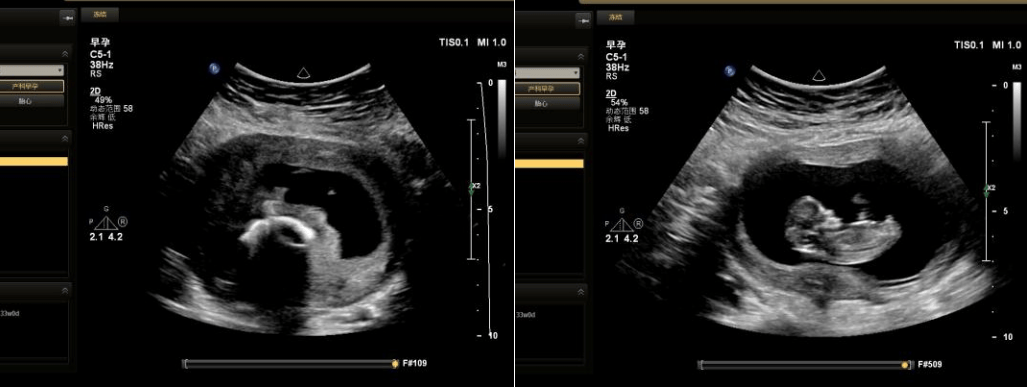

这是一位因月经紊乱、经量减少来就诊的患者超声检查后的疑惑,但超声检查的结果显示,她已经带环妊娠快三个月了。

上述患者的带环宫内妊娠,多与带器失败有关。这种情况可根据本人意愿,选择人工流产或产科医生指导下继续妊娠。如坚持继续妊娠,需更加应注意孕期的监测,以防自然流产、感染、胎儿宫内发育迟缓、早产或死胎的发生。